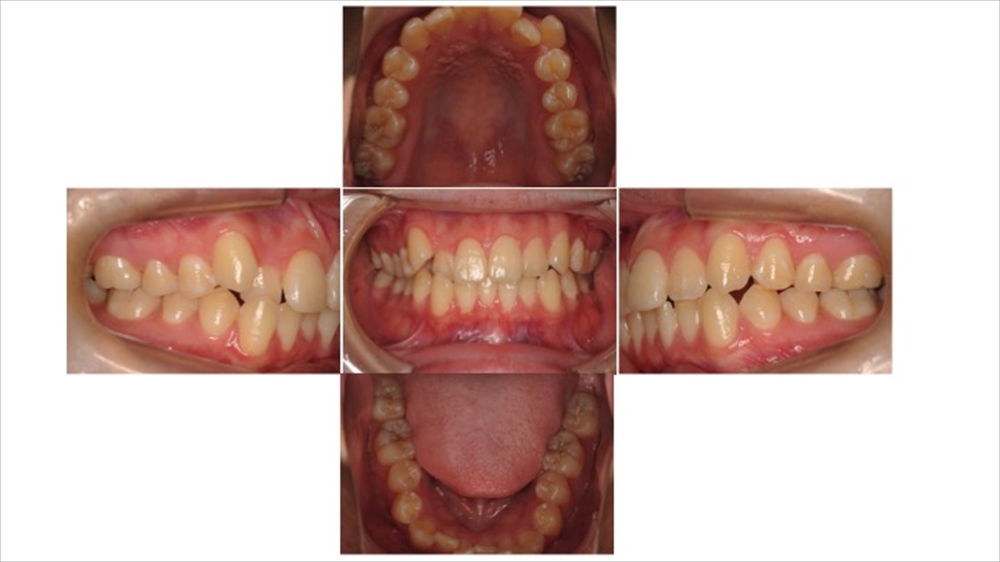

実際に撮影した写真をご案内します。

上記の写真がお口を撮影した写真です。

このように上下左右、正面から撮影することで患者さまのお口の状態を把握し、記録します。

ちなみにブログの最初にご紹介したお口の写真は精度の低い撮影例です。

ぱっと見わかりませんが、5枚ある写真の内右手の写真に違いがございます。

違う点としては“平行に確認しやすいように撮影できているかどうか”という点になります。是非、見比べてみてください。